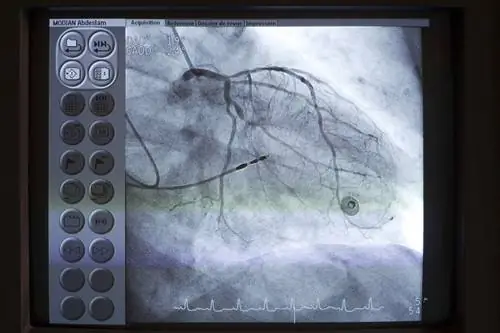

Ангиография почти всегда выполняется во время процедуры, которая включает в себя введение красителя в ваши сосуды, чтобы их можно было визуализировать с помощью изображений, обычно рентгена или внутрисосудистого ультразвука.

Краситель вводится через катетер, в то время как записывается серия быстрых рентгеновских изображений, на которых создается видеозапись кровотока через камеры сердца или коронарные артерии.